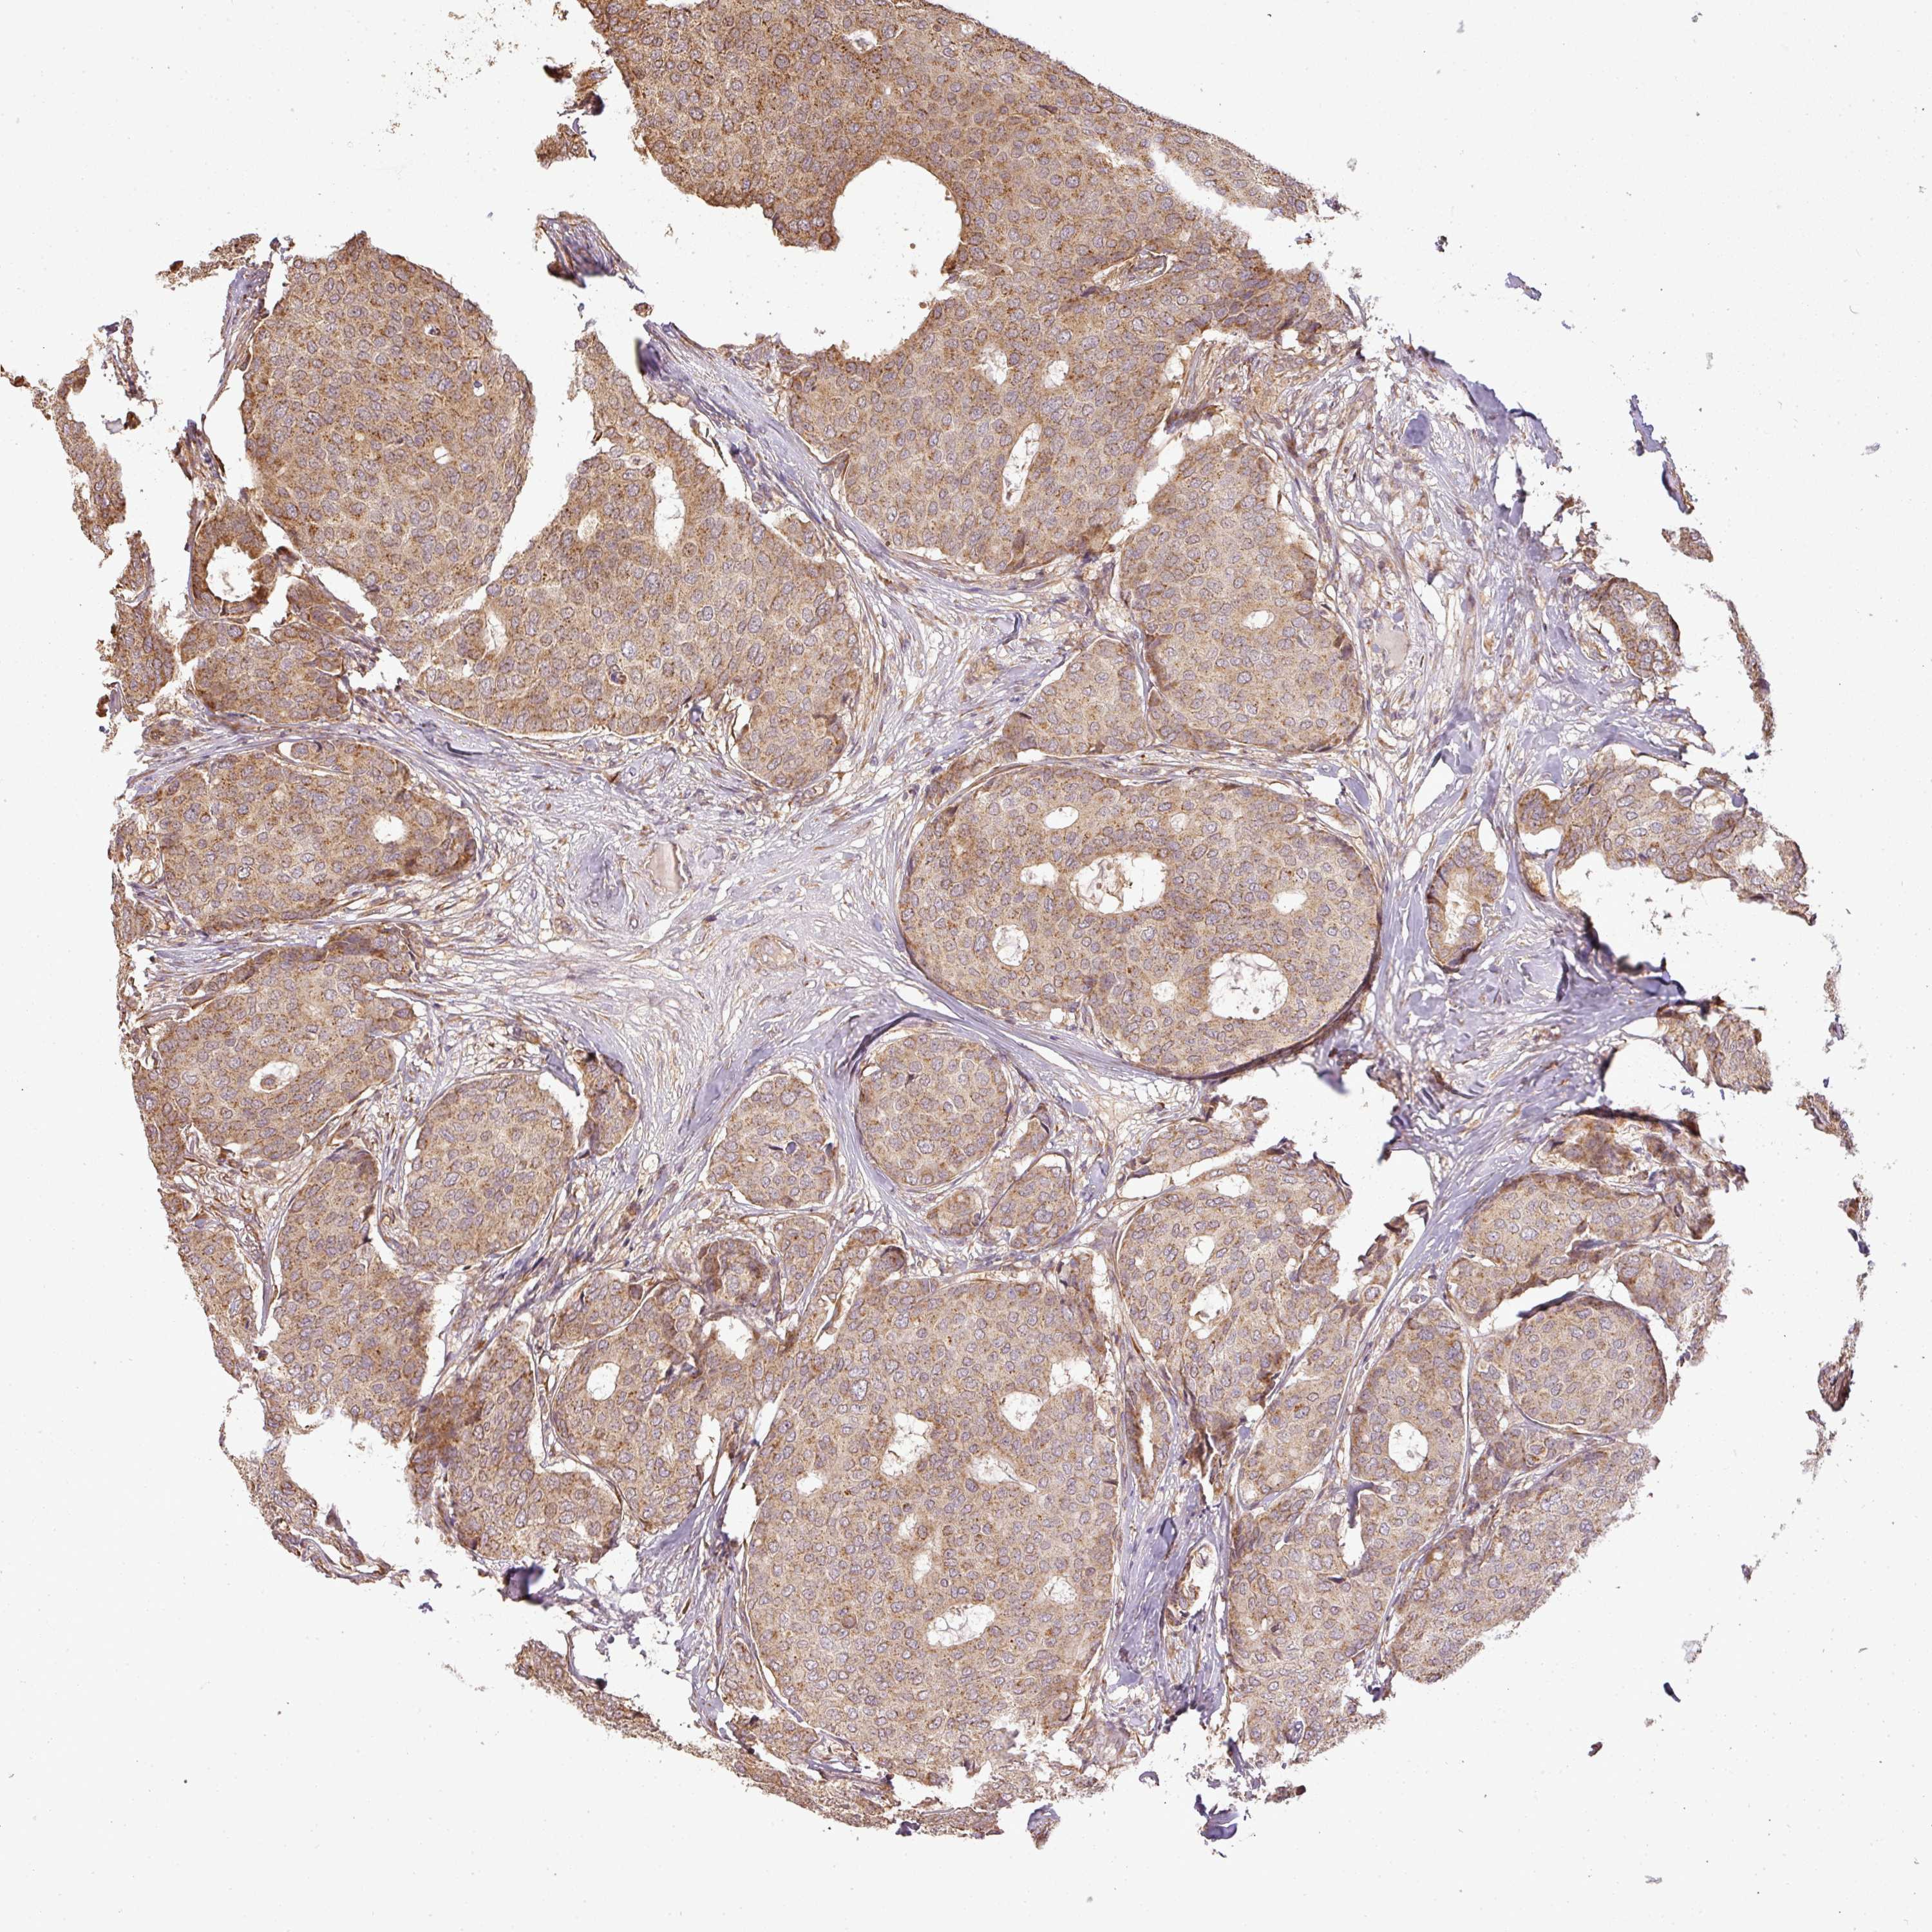

CANCER BREAST CANCER Show tissue menu

BRCA TCGA BRCA VALIDATION PROTEIN EXPRESSION